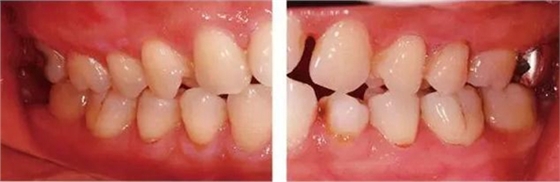

●參考病例① 35歲女性

35歲女性。妊娠4個(gè)月。過去雖然接受過刷牙指導(dǎo),但菌斑控制狀態(tài)依然不理想?;颊哂邪l(fā)現(xiàn)自己刷牙時(shí)牙齦出血。

●參考病例② 25歲女性

25歲女性。菌斑控制狀態(tài)不好。齦溝除磨牙處外全在3mm以下,X光照片上左上、右下、左下的第一磨牙上有垂直性骨吸收。這個(gè)病例是參考病例①10年前的狀態(tài),是典型的侵襲性牙周炎局部型。